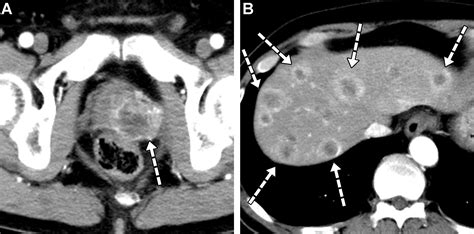

Abdominal CT Scan Provides detailed cross-sectional images to identify lesion size and location.

MRI with Contrast Highly sensitive; often used to differentiate benign lesions from metastases.